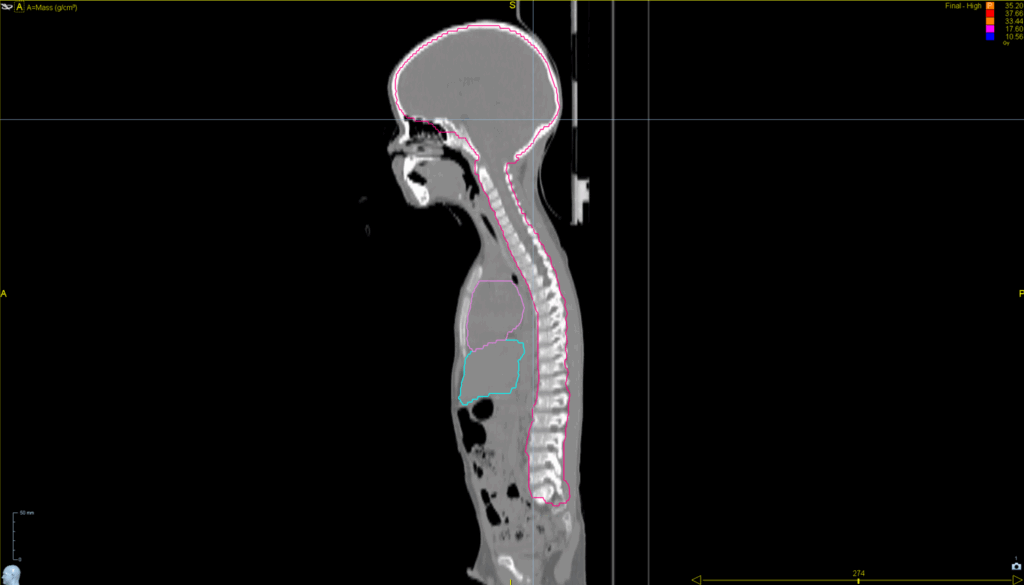

Lung SBRT with Synchrony® Fiducial Tracking™ and Respiratory Modeling

< View All Plan Studies RADIXACT SYSTEM Lung SBRT with Synchrony® Fiducial Tracking™ and Respiratory Modeling Case History AGE: 76-year-oldGENDER: Male Medical History Immidiate tolerance: Grade II dermatitis with eyelid edema, Grade I conjunctivitis resolved with Sterdex Diagnosis: Squamous cell carcinoma of the right lower eyelid Planning CT Images Treatment Plan Images ClearRT® Images Treatment […]